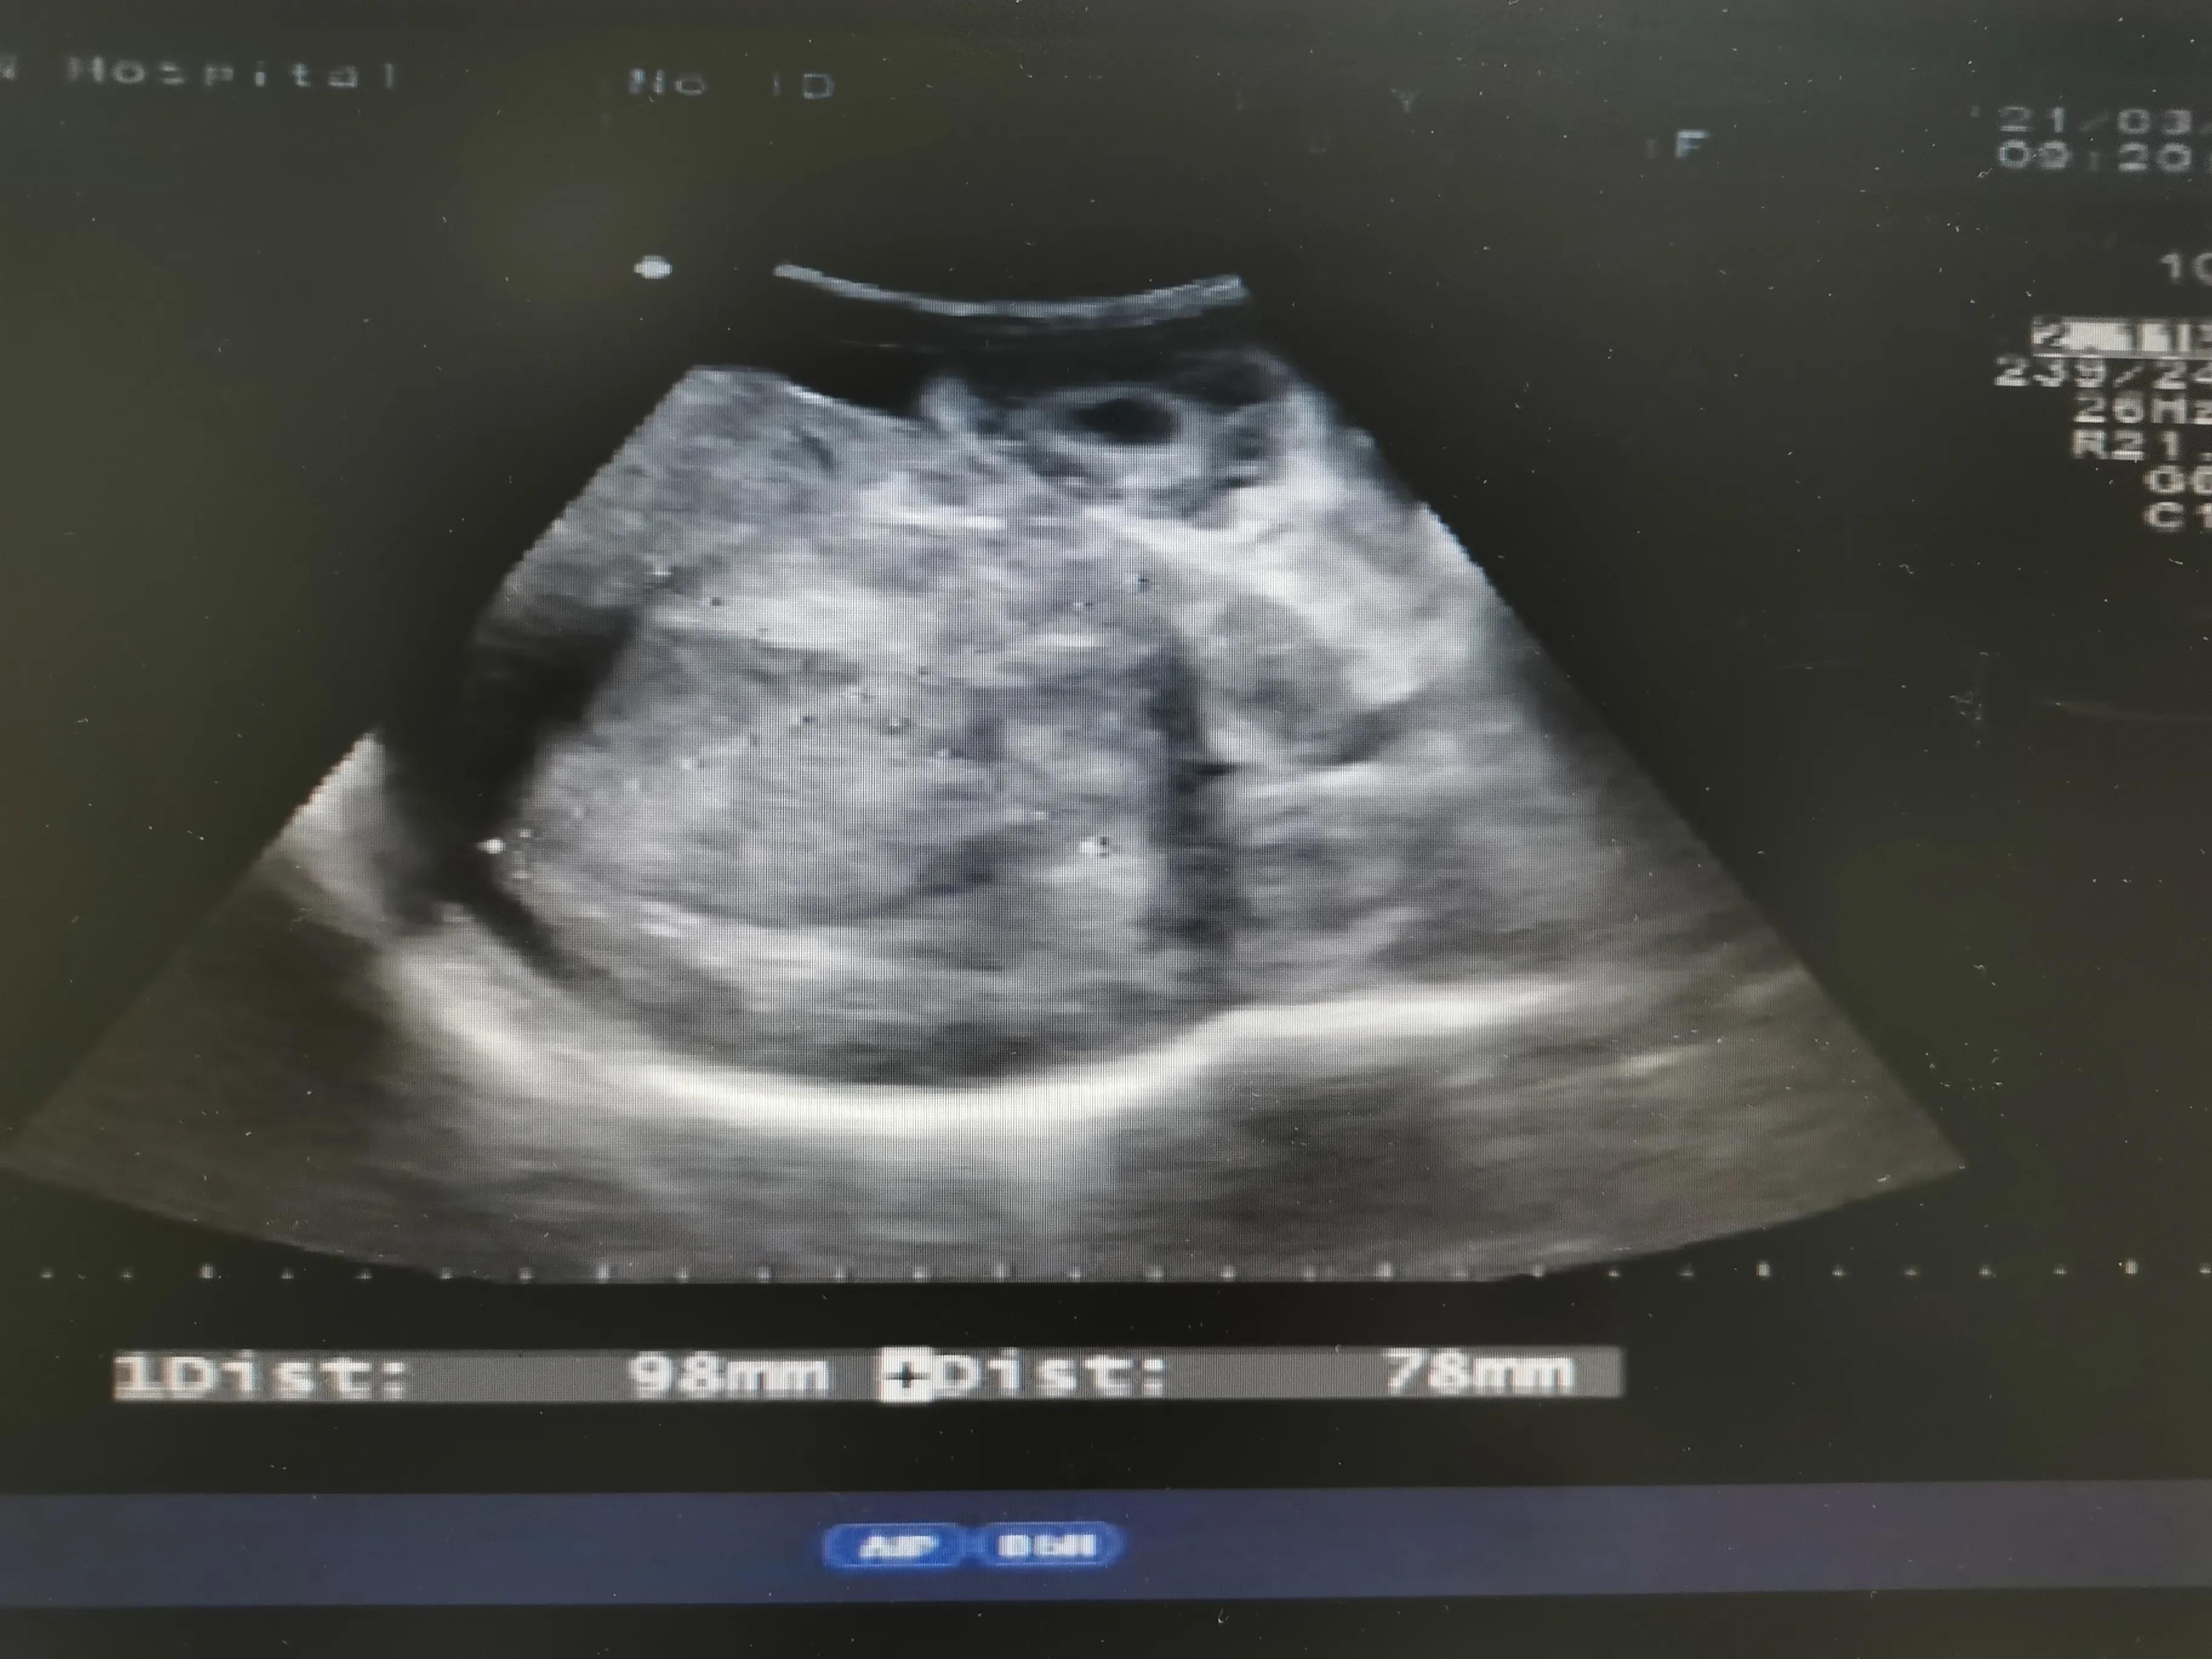

下面我们看看肝硬化失代偿期并肝癌病人肚子里面的情况

肝癌肿块

血管内癌栓形成